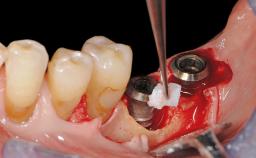

Resective Surgical Treatment of Peri-Implantitis Including Implantoplasty

In this case, Myroslav Solonko, Ignacio Sanz Sánchez and Mariano Sanz present a treatment that aims to eliminate exposed implant threads by modifying the implant surface, converting a moderately-rough surface into a smooth surface.

A 63-year-old male patient was referred to the post-graduate periodontal clinic of the Complutense University of Madrid for the treatment of peri-implantitis. According to the patient’s record, all his maxillary teeth had been extracted ten years previously due to severe periodontitis, and a full-mouth implant-supported restoration on eight implants was placed. No supportive periodontal therapy was provided apart from occasional check-ups by the restorative dentist.